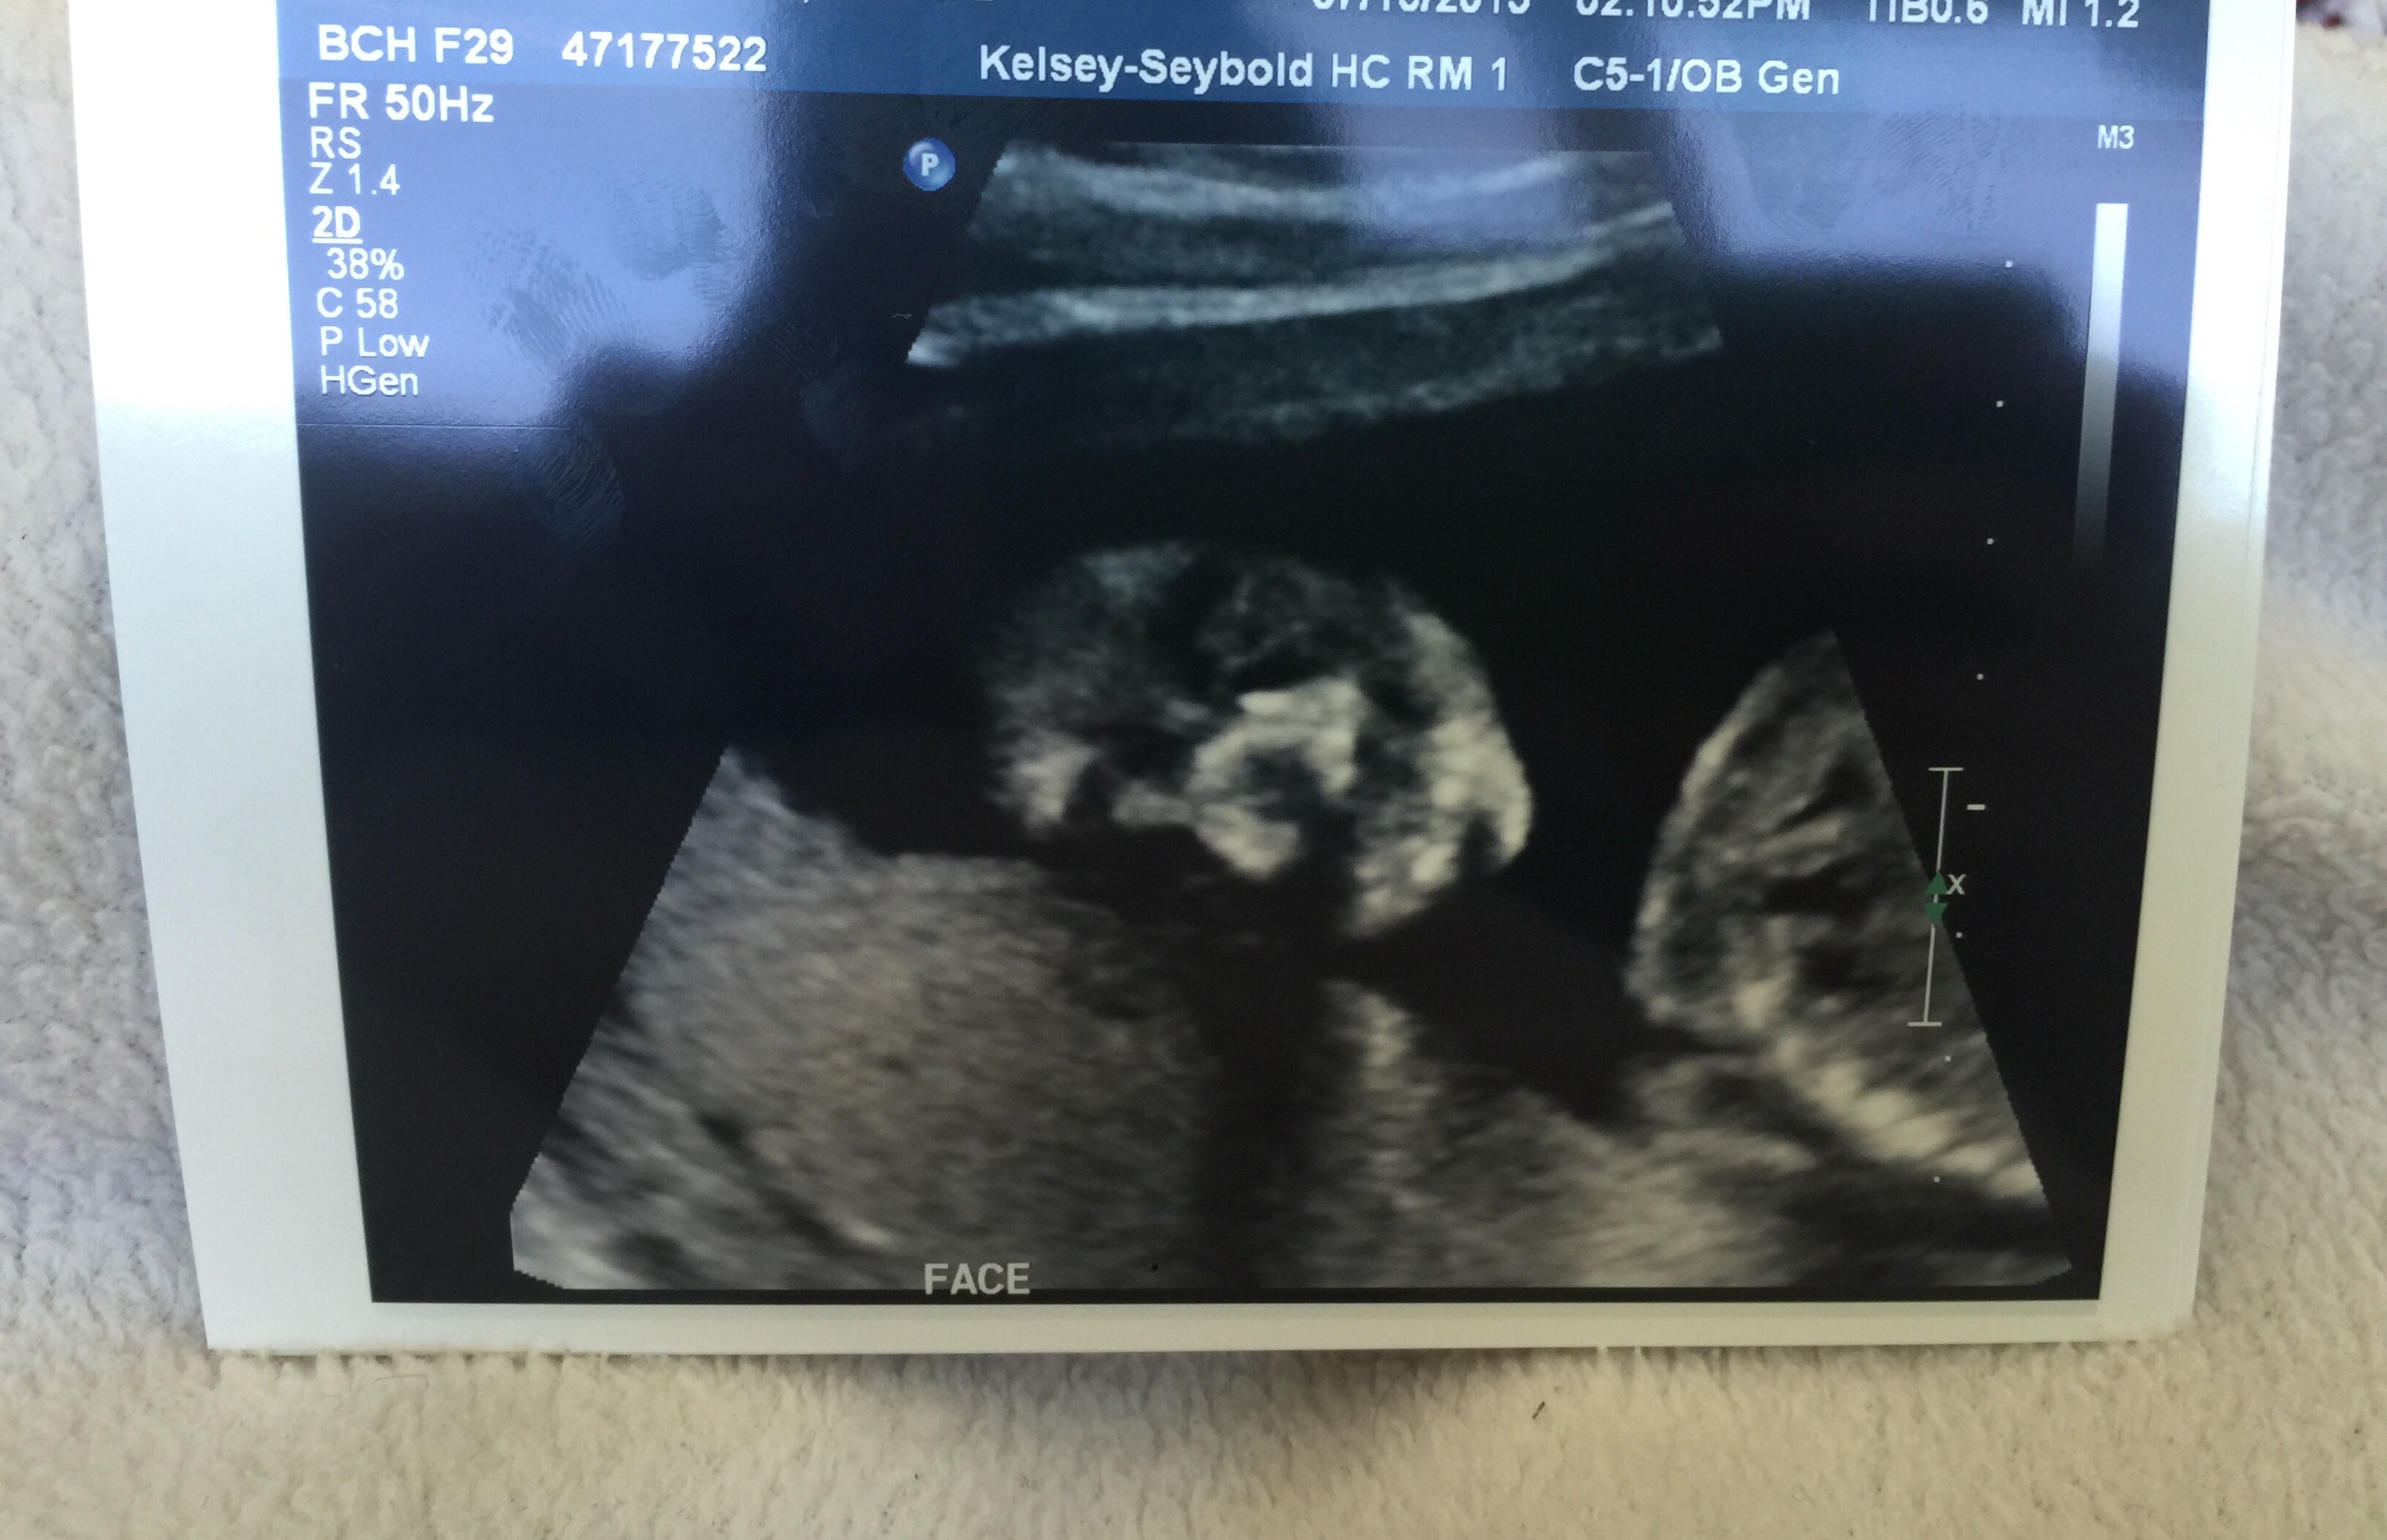

Had mine 7/9/15 @ 19 weeks exactly. My perinatologist was particularly looking for any heart defects and abnormalities in the kidneys or urinary tract--my little girl has a single umbilical artery (SUA; aka "two-vessel cord) and this abnormality has been correlated with abnormalities in these two organ systems. They did the fetal echo in conjunction with the anatomy scan and my perinatologist said everything looked great. This was my main concern so I feel as though a huge weight has been lifted. I was on the US table for over two hours so that she could get sonogram "video" of the heart and look at the kidneys more in depth too so it was definitely my longest US to date. We knew the sex was a girl from a prior 15w scan but it was confirmed again. She is measuring in the 33rd percentile, and we conceived 10 days after my last period, not 14, so she is actually likely a bit smaller. This is par for the course for SUA babies so my OB has already informed me we will be getting serial growth scans from here on out, Doppler velocimetry at each visit, as well as NST's weekly or twice weekly starting at 32 weeks (much earlier if she declines in growth percentile). SUA babies--mine LO's is "isolated", meaning it is not associated with a chromosomal abnormality or a organ defect--are at a significantly higher risk for IUGR and even stillbirth, thus the very close monitoring. If she drops below the 10th percentile in terms of growth it will be time to consider delivering via c-section since this would indicate she isn't getting the nutrients she needs due to the cord abnormality and would be "better out than in." My OB said he would likely not let her go past 37 weeks, so my little one could arrive closer to mid-November as opposed to closer to her due date of 12/3. Just seeing a beating 4-chambered heart that is structurally and functionally normal, two kidneys and a normal urinary tract just made my month. Literally.

We had our AS today and everything looked great! The tech said if she had seen something unusual she would have told the doctor and they would have talked to me but she said it looked great. She also confirmed it's a GIRL! We had a sneak peak last month and she just confirmed it (good thing because we already bought so many girl clothes while on vacation last week)! LO was all curled up in the bottom of my uterus and there was so much space up top... She was all cozy, moving around and then she got the hiccups! It was hard to get some of the shots thought because she was curled up so I had to go into all kinds of positions... Ouch! So worth it though!